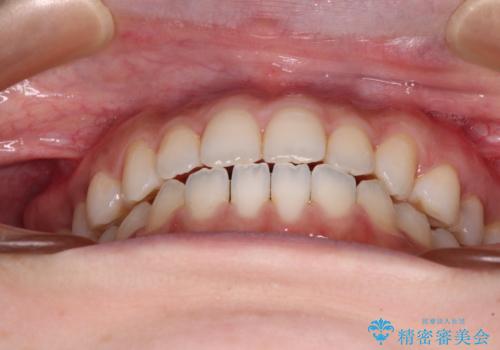

舌突出癖で口元が開いてしまう 舌トレーニングを行ったインビザライン矯正

- 前歯の上下スペースと前歯の隙間を気にして来院された患者様です。

インビザラインにより上下の前歯の隙間を閉じていくこととしました。

上下の隙間に舌が入り込むことが、すきっ歯やオープンバイトの原因であったため、舌の筋肉のトレーニングも並行して行い、後戻りの抑制を図りました。